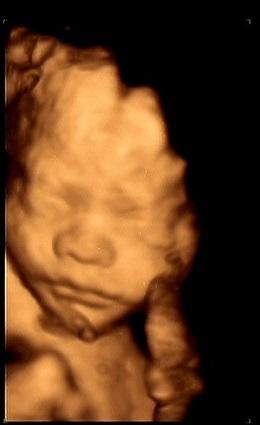

四维彩超即四维医学彩色超声成像技术。它 是在三维医学彩色超声成像的基础上加上第四维的时间矢量,能够实时显示三维立体图像。

三维彩超、四维彩超的图像是后期生成的,其成像基础仍然是普通彩超。通过设备中的图像转换软件,将获取到的平面图像转换成三维、四维的立体图像。

说得更大众化一点,普通彩超显示的是图片,三维彩超显示的是静态立体图像,四维彩超显示的是动态立体图像。

1.胎儿面部畸形: 如唇裂、腭裂等。